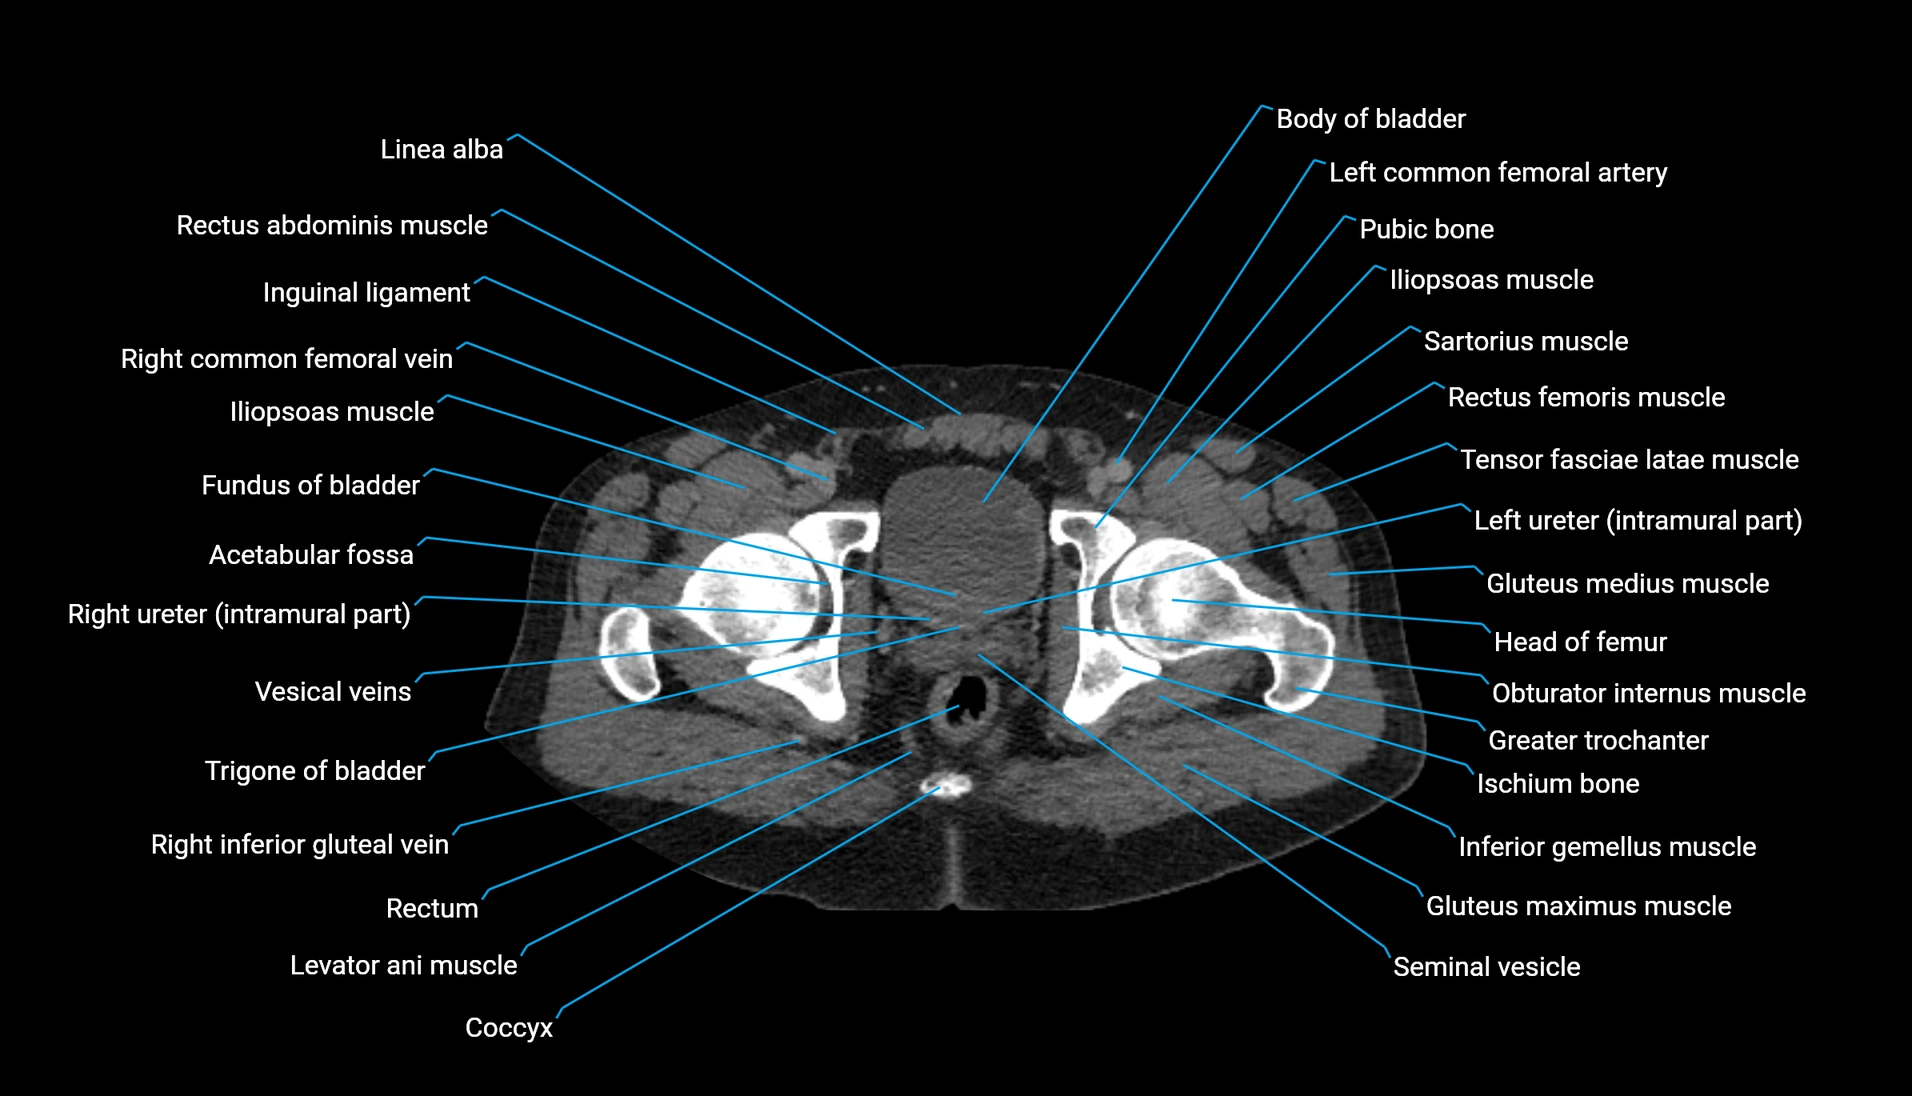

CT Appearance

Non-contrast CT:

-

Demonstrates cortical bone of acetabular rim in excellent detail

Detects fractures, dysplasia, retroversion, or bony overcoverage (pincer impingement)

3D reconstructions used in preoperative hip surgery planning

CT Post-Contrast (CT Arthrography):

Joint contrast outlines the acetabular labrum, cartilage, and margin

Demonstrates labral tears, cartilage defects, and subtle bony abnormalities

Alternative to MR arthrography in patients with MRI contraindications

CT VRT 3D image

CT image